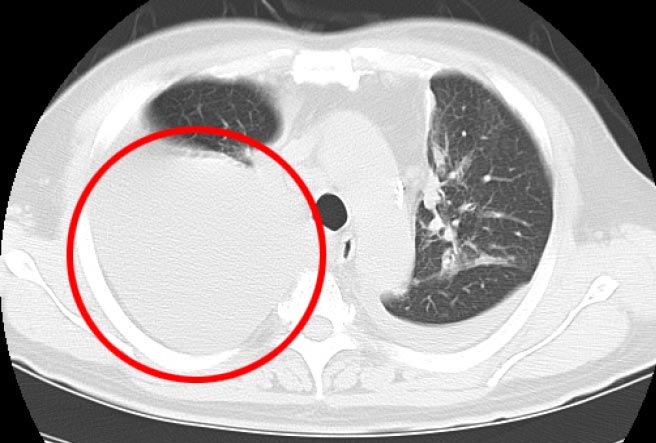

治療前のCT検査結果

治療前CTでは右肺に大量貯留した胸水が認められました。